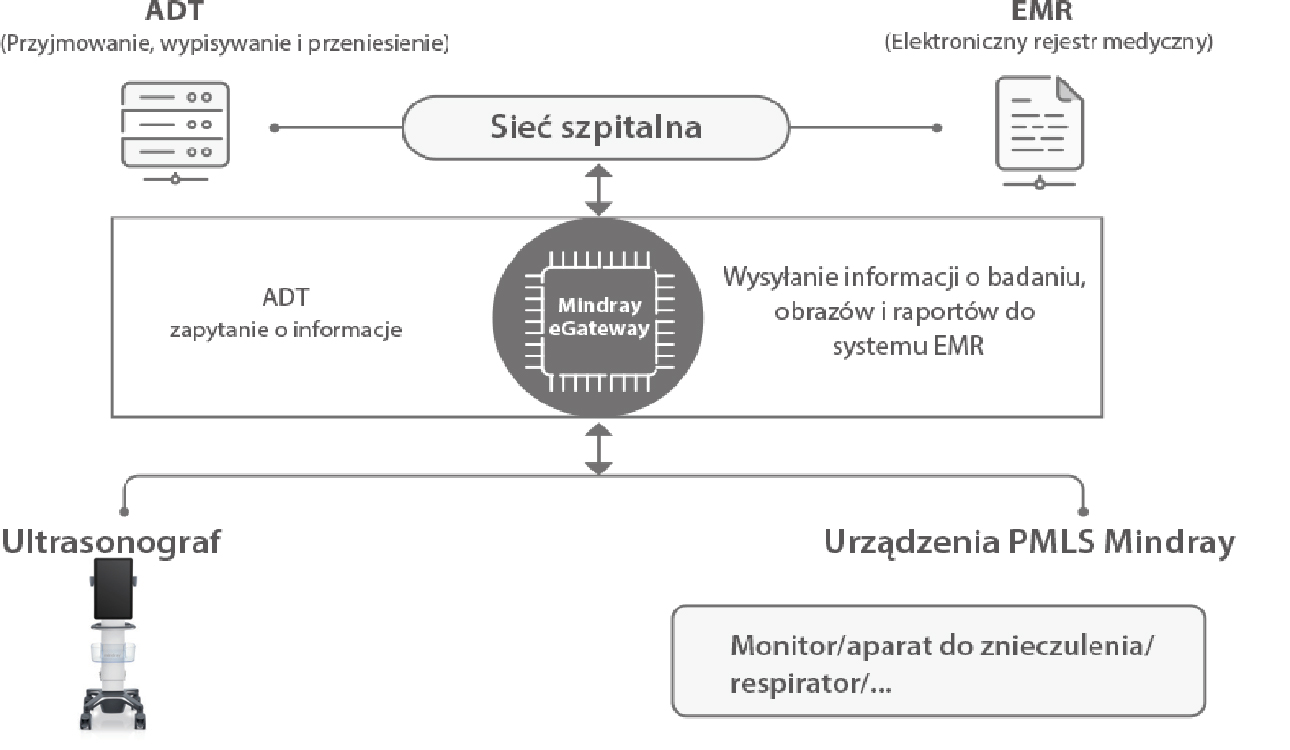

Aparat ultrasonograficzny TE9 zaprojektowano tak, aby rozszerzy? mo?liwo?ci diagnostyczne na oddzia?ach ratunkowych oraz intensywnej opieki. TE9 posiada wygodny i du?y ekran dotykowy oraz zaawansowane funkcje, kt├│re wspieraj? diagnostyk?. Inteligentne aplikacje kliniczne u?atwiaj? wykonywanie pomiar├│w, co pozwala sprawnie przeprowadza? badania i czynno?ci nawet w dynamicznym ?rodowisku pracy.